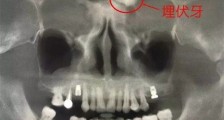

- 男子额头长一颗牙 这竟是他得怪病的原因难以置信【热点】

- 按照常识,只有嘴巴里才有牙齿,但是却有一男子额头长一颗牙了,想必很多人对此状况也是从未见过吧,所以很难相信牙齿竟然可以长在额头上的,可这却真实的发生的了,该男子也因为这颗牙...

- 额头竟长了一颗牙怎么回事 额头藏牙原因揭秘真相令人惊【热点】

- 要是有人跟你说,额头上长有牙,你信吗?近日,在深圳某医院里,一名中年男子的额头,竟然长了一颗牙!在经过CBCT拍摄发现,该名男子额头“藏”有牙,这还真是闻所未闻的世间“奇事”啊!下面,就...